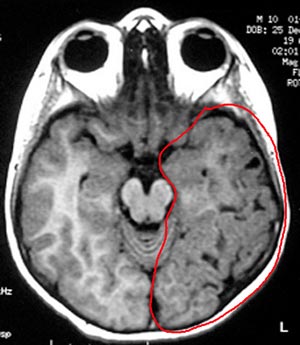

5a) Displasia cortical frontotemporal (lobos frontal e temporal)

Figura 67 - Ressonância nuclear magnética pré-operatória.